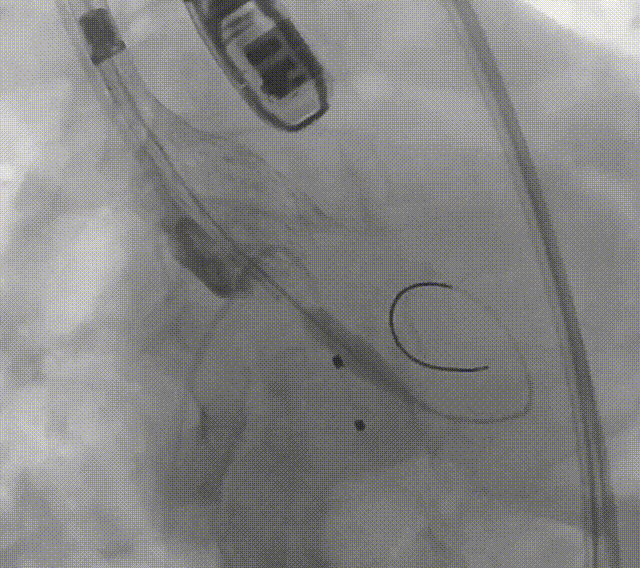

主动脉根部造影

初始定位

预释放后定位

首次释放弹出

再次释放

深度评估

释放体位

LAO体位

释放脱钩

造影评估